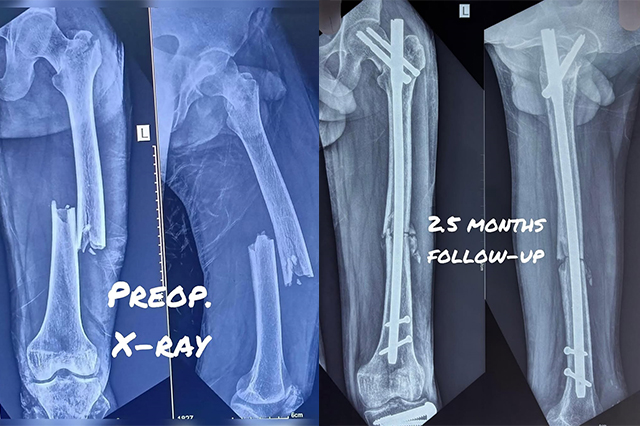

Hip-Knee-Replacement